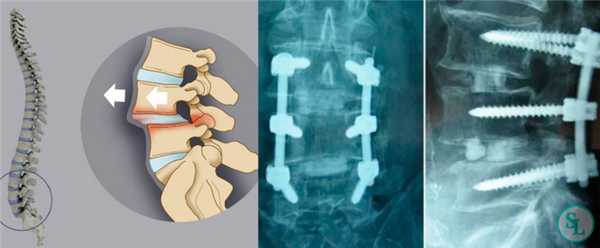

- Спондилолистезы (смещение позвонков) - патология, обусловленная смещением или деформацией межпозвоночных дисков. Осуществляется замена титановым имплантатом межпозвоночного диска или самого позвонка с последующей иммобилизацией.

- Стенозы (сужение просвета) позвоночного канала. В ходе декомпрессионной фазы операции удаляются стенозирующие факторы (межпозвоночные грыжи, опухоли, дегенеративно-дистрофически измененные позвонки). После этого, на стабилизационном этапе, производится фиксирование оперированного сегмента при помощи винтов и транспедикулярной системы.

Кейдж представляет собой полую конструкцию, подобранную по диаметр тела позвонка. Он устанавливается вместо удаляемого межпозвоночного диска и жестко фиксирует пространство между телами позвонков. Такой вид фиксации применяется при переломах позвоночника или при дегенеративно-деструктивных процессах, приводящих к полному или частичному разрушению межпозвоночных дисков.

Сам имплант изготовлен из титанового сплава или керамики, после установки его полость заполняется специальным цементом, сходным по структуре с костной тканью.

В реабилитационном периоде межпозвоночный кейдж и окружающая костная ткань взаимно прорастают друг в друга, обеспечивая, со временем, полное восстановление функции поврежденного сегмента позвоночника.